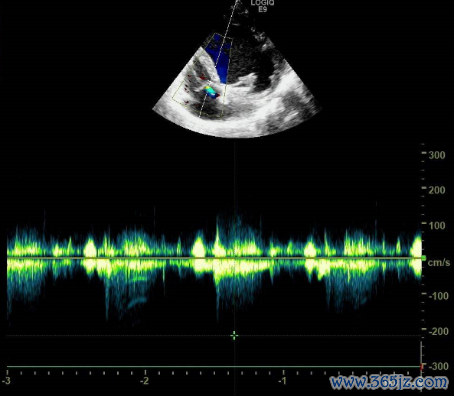

超声心动图:

左心大,左房前后径44mm,左室前后径71mm,右心各房室腔、主动脉及肺动脉内径简单;

心室壁及室远离厚度简单,各节段指令幅度减低,左室侧壁、后壁中段及心尖段肌小梁加多、呈珊瑚状改动,纰缪与室腔重迭,肌层变薄;

二尖瓣中-多量返流,三尖瓣一丝返流,主动脉瓣一丝返流,心功能减低,左心室射血分数(LVEF)30%(图2-5)。

图2 超声心动图效劳

图3 超声心动图效劳

图4 超声心动图效劳

图5 超声心动图效劳

超声效劳一出,会诊就明晰了,然而波仔的脸上却仿佛写满了问号。